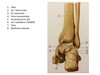

Nævn de 7 uregelmæssige fodrodsknogler - og forklar hvilken fod du ser på billedet. + Hvor fleksions og sup/pro aksen går.

Det er højre fod, begge af dem.

Spot de 8 punkter

beskriv de forskellige punkter.

Spot punkterne

Spot posterior